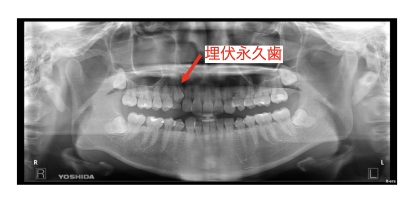

上下顎叢生(上下前歯のガタガタ)、過蓋咬合(咬み合わせが深い)、右上埋伏歯(大人の歯が埋まっている)ケースです。

初診時には、右上の犬歯が骨の中に埋まっており乳歯が残っています。治療計画では乳歯を抜歯して、埋まっている永久歯を引っ張り出してくる治療計画を提案し、治療を開始しました。

装置はラビアル(上下表側)で、抜歯したスペースに埋まっている永久歯を牽引し、排列しました。また、上下の叢生(ガタガタ)と過蓋咬合(咬み合わせ深い)の改善を行っています。

主訴 永久歯が埋まっている。

年齢・性別 30歳 女性

お住まいの地域 東京都大田区

治療方針 乳歯抜歯し、永久歯の開窓牽引、上下前歯の叢生(ガタガタ)および過蓋咬合改善

抜歯部位 上顎右側C

使用装置 ラビアル(上下表側)、顎間ゴム

治療期間 3年6か月

治療回数 24回

リテーナー クリアリテーナー